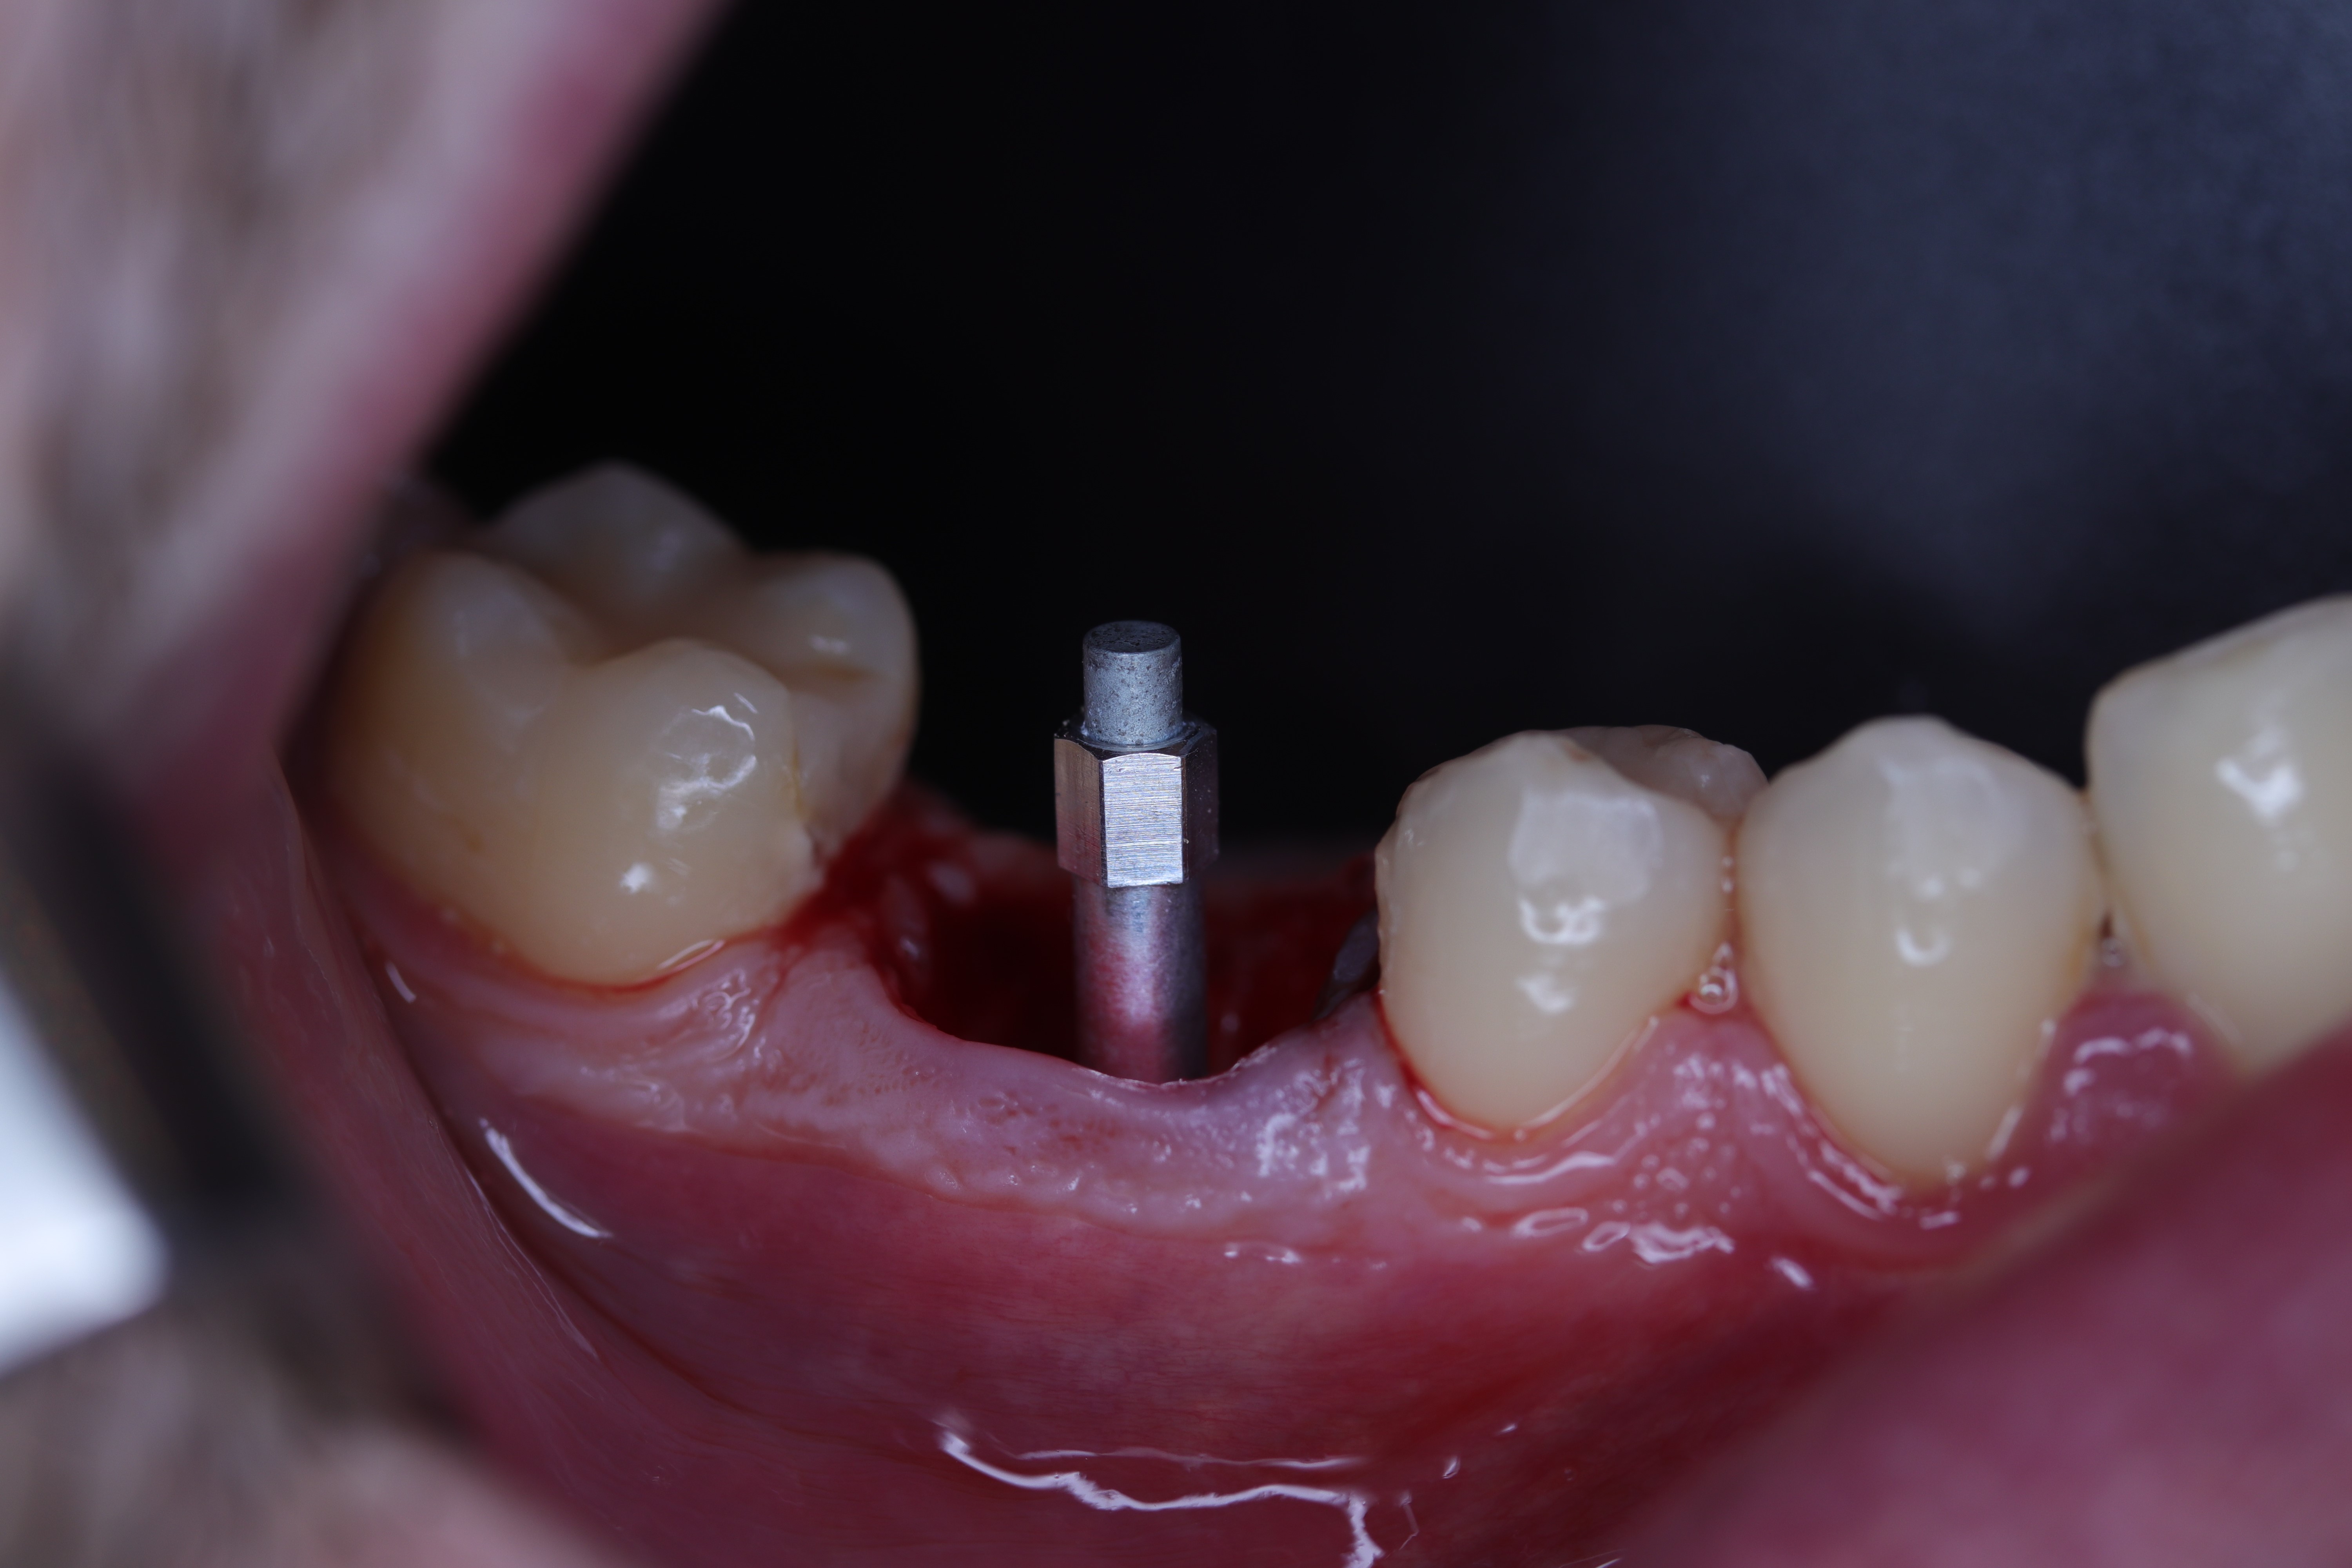

Maxillary Central Incisor Implant Supported Crown Brief Case Report Dental Implant Isq Supported by more than 1400 scientific. Four levels of coverchoose your plan The rfa is a reliable indicator for. Implant stability is a prerequisite for successful dental implants and osseointegration. Introduced rfa as a quantitative method for assessing implant stability (7). To determine the status of implant stability, continuous monitoring in an. Isq, or implant stability quotient, is a scale. Dental Implant Isq.

From dentistry.co.uk